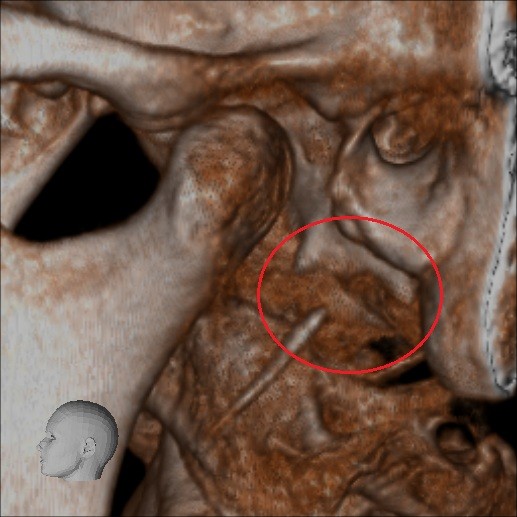

Below are some screenshots from my Cone Beam CT scan and the report linking possible ES. I have more Regular CT scans I could possibly share and/or if you would like me to get possible better angles from the Cone Beam CT scan let me know. But as of right now I’m at a loss as what to do going forward. I do have an MRI with and without contrast of the Cervical Spine Scheduled, but that’s due to the doctor’s (the doctor that dismissed it as ES and one doctor that wants to follow up and learn more on it) wanting it.

- Now onto this year, I finally got better back to full health in late November early December 2024 and sadly started to get another sinus infect in January and still no answers to why. I just happen to be watching YouTube when a Dentist had said that your teeth could be linked to sinus issues causing sinus infections and normally the only way to tell if this is the case is to get a Cone Beam CT scan. I then thought this could be another lead to find out why I keep getting sick as I did when I was 10 have my first top premolar on my left side removed against what I wanted as they said my teeth were too crowded and it needed to be removed so I could have braces (which that dentist didn’t even do my braces anyway). But I thought when he removed it if a small piece of the root was still in there as he just broke out the tooth without removing it via surgical means that that could cause an abscess in my Left Maxillary Sinus where infections always start. So, finally I was able to find a place that would give me a Cone Beam CT scan back in February of this year all while I was just starting to get sick from my infection. Anyway, I finally got the report in March and found out oddly my Left side is mostly normal other than mucus polyps, but I have a few other issues (I have attached the report below). This report is where I first found out about Eagle Syndrome as it states I might have Calcified Ligaments and further testing is needed to confirm. It was only after this report and looking up what Eagle Syndrome was that I can say I have almost every symptom that has ever been reported. Sadly, I couldn’t find anyone in my State at the time that work with Eagle Syndrome and when I did was about a week before I found this site and the doctor I did see seemed to dismiss me as another hypochondriac and you can’t have it as you don’t have Vertigo type Dizziness, my styloid are normal length and I don’t have neck pain equivalent to having to be in a neck brace. Not only this she only looked at my CT scan from a week earlier that I had got in Emergency. The Emergency visit was due to the fact at 8PM that night I had pain in my Right Mastoid Bone, and I was starting to get an earache. I went to lay down and took pain meds and an ice pack in hopes to reduce the pain and swelling. I couldn’t sleep due to the pain and came upfront about 10PM. 10:21PM I couldn’t take it anymore and started to stretch my neck and I felt a huge snap and heard a load pop, all the pain just felt like it disappeared. One minute later, I had a massive pain that spread just like when you get an IV that stings, but it felt like someone was trying to murder me and stabbed a knife into the right side of my skull. I was in so much pain that I was hunched over, and we had to have an ambulance called. I thought I was having an aneurism and my mother thought I was having a Stroke (very rare ES Symptom). When the ambulance arrived, they took my vitals, and my blood pressure was 148/110 with a pulse in the high 90’s low 100’s. Luckily the pain had subsided enough that we were able to go to emergency without the ambulance ride, but while I was in emergency the pain had spread to my left side of my head and now felt like someone had taken a clothes iron and stuck it on my head. Any breeze moving my hair was pure agony and I couldn’t lay my head on a pillow without that burning pain. According to emergency though I must have just had a Mastoid Process infection and it burst. Luckily the pain went away by the time I went to the Doctor for ES, but like I said before they were of no help.